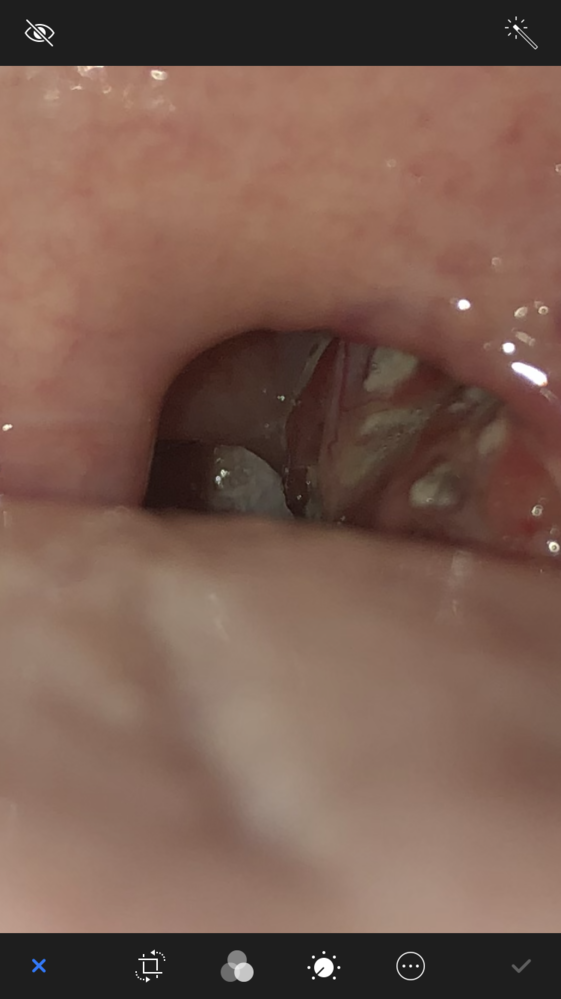

膿栓や扁桃腺にできる写真塊と咽頭クラミジアとは 膿栓や扁桃腺にでき 性病 性感染症 Std 教えて Goo

これって喉のクラミジアですか 白い部分は膿栓と思います 俗に言う臭 Yahoo 知恵袋